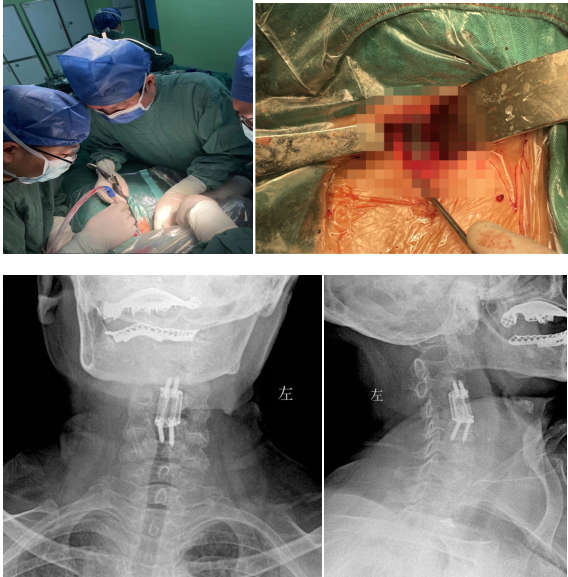

經(jīng)過多學(xué)科會(huì)診(MDT),完善術(shù)前相關(guān)準(zhǔn)備后,由蘇光輝主任主刀,帶領(lǐng)團(tuán)隊(duì)錢軍、鄧三東等,精準(zhǔn)完成病灶清除、椎管減壓、植入3D打印cage等流程,在麻醉師、手術(shù)室的全力配合下,整臺(tái)手術(shù)一氣呵成,手術(shù)順利。

術(shù)后影像學(xué)顯示,植入內(nèi)植物位置滿意,與終板匹配性良好,穩(wěn)定性佳。術(shù)后患者生命體征平穩(wěn),癥狀明顯緩解,活動(dòng)良好,目前已出院。